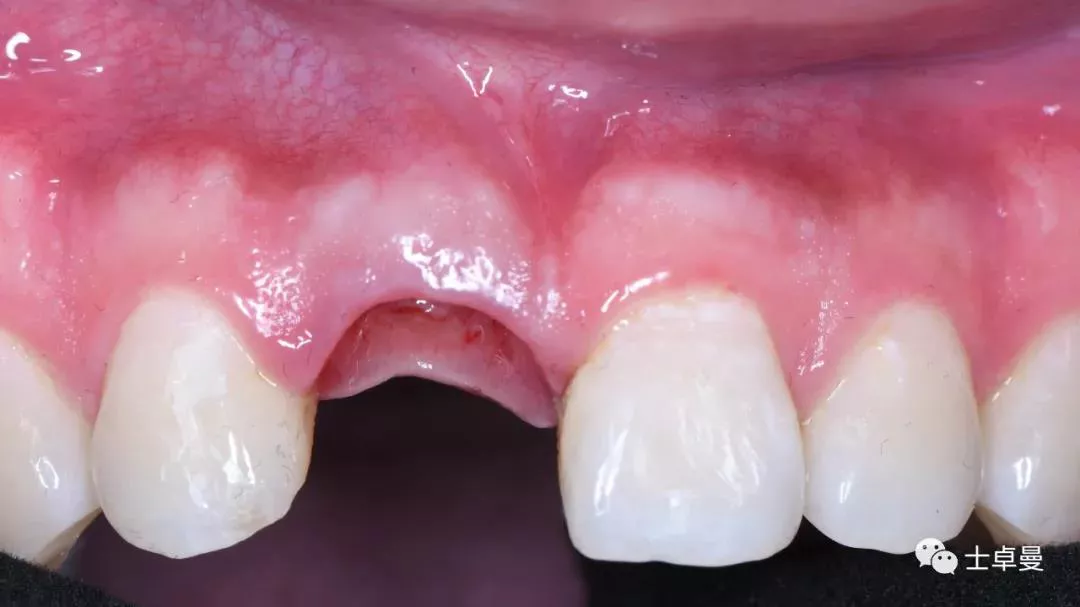

术后1个月,取下马里兰桥,可见骨弓轮廓可,软组织无炎症

术后4个月复查,软组织无炎症

试戴种植体支持式临时修复体,塑型软组织

临时修复后2个月,龈缘及龈乳头位置理想,软组织健康